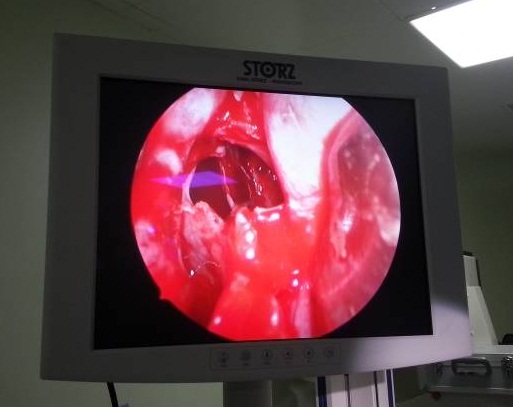

كربلاء: رفع ورم في الغدة النخامية من الدماغ  بالناظور وعن طريق الأنف

نجح فريق طبي من مدينة الأمام الحسين(ع) الطبية مكون من الدكتور عادل هادي المسعودي اختصاص (أنف وإذن وحنجرة ورأس ورقبة)والدكتور امجد الدفاعي (اختصاص الجمله العصبية) وطبيب التخدير الدكتور عادل خضير بالإضافة الى الممرض المساعد جمال محمد من اجراء أول عملية دقيقة في كربلاء لرفع ورم كبير في الغده النخامية من الدماغ بواسطة الناظور وعن طريق الأنف , وقال الدكتور عادل المسعودي في تصريح خصه لوكالة نون الخبرية اليوم الخميس ان العملية اجريت لسيدة تبلغ من العمر 35 عاما راجعت المستشفى وهي تشكو من صداع مستمر وبعد اجراء التحاليل الطبية وفحوصات الرنين والمفراس تم تشخيص ورم كبير (4×6)سم في الغدة النخامية للدماغ وتابع. أدخلت المريضة على اثرها الى صالة العمليات وأجريت لها العملية بواسطة الناظور من خلال عمل فتحة في داخل الحاجز الأنفي الوسطي والدخول للجيوب الانفية ومنها الى قاع الدماغ ثم الى الغدة النخامية والوصول للورم بعد اخضاع المريضة للتخدير العام وتم ازالة الورم بالكامل وترقيع المكان المرفوع منه والمريضة الان تتمتع بصحة جيدة ودون اي مضاعفات فيما ارسل الورم المرفوع للفحص عن طريق زرعه بالمختبر واصفا العملية بالدقيقة والصعبة كونها بمنطقة محدودة جدا(2ْْْْْX2) سم وبين الشرايين والأعصاب وان فقدان او نزف اي عصب او شريان يتسبب في شلل كامل لجسم المريض وهو ما يعقد اجرائها عن طريق فتح الجمجمة كما كانت تجرى سابقا مثل هكذا عمليات لافتا الى ان اي قطرة دم اثناء العملية بالناظور تتسبب بانعدام الرؤية في عدسة الناظور مما يضطر الملاك الطبي الى استخراجها لتنظيفها مشددا على ان العملية عن طريق الناظور أكثر امانأ. وكالة نون خاص